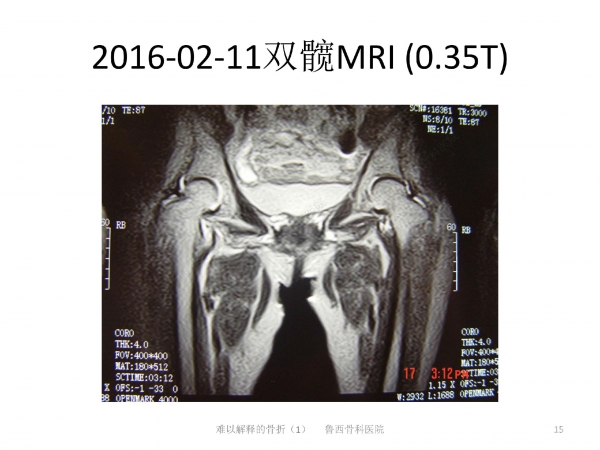

难以解释的骨折之一

导语:在日常生活中,因老年人普遍存在骨质疏松的问题,滑倒很容易造成髋部骨折。90%的老年人发生髋部骨折多因摔倒引起。然而有些骨折完全没有外伤,前驱疼痛,属于不典型骨折。来自鲁西骨科医院的王书军医师、段玉民医师,为我们带来一例“难以解释的骨折”病例,并做了初步探讨。请详见下文分解。